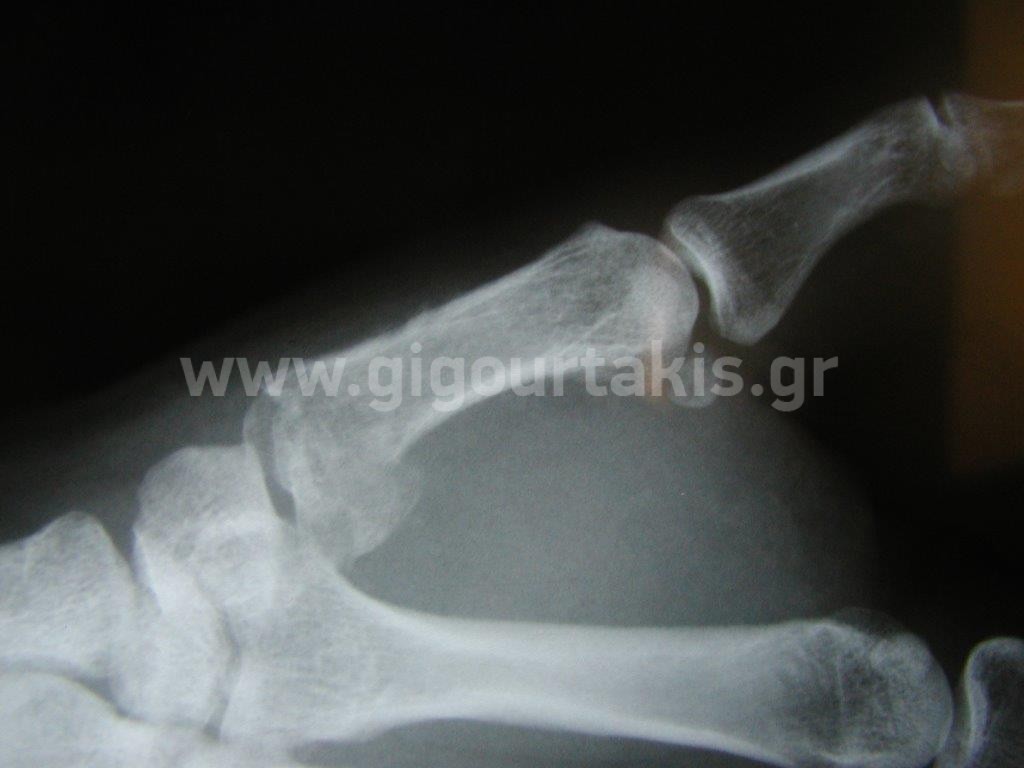

ΚΑΤΑΓΜΑ ΜΕΤΑΚΑΡΠΙΩΝ ΚΑΤΑΓΜΑ ΑΝΤΙΧΕΙΡΟΣ- SKIERS THUMB ΣΥΝΤΗΡΗΤΙΚΑ ΠΕΡΙΣΤΑΤΙΚΟ 1 01. 02.ΑΡΧΙΚΗ ΚΑΜΨΗ ΑΝΤΙΧΕΙΡΟΣ 03.ΑΡΧΙΚΗ ΕΚΤΑΣΗ ΑΝΤΙΧΕΙΡΟΣ Στις κατηγορίες:ΑΝΩ ΑΚΡΟ, ΑΚΡΑ ΧΕΙΡΑ, ΚΑΤΑΓΜΑ ΑΝΤΙΧΕΙΡΟΣ- SKIERS THUMB ΣΥΝΤΗΡΗΤΙΚΑ, ΚΑΤΑΓΜΑ ΜΕΤΑΚΑΡΠΙΩΝ